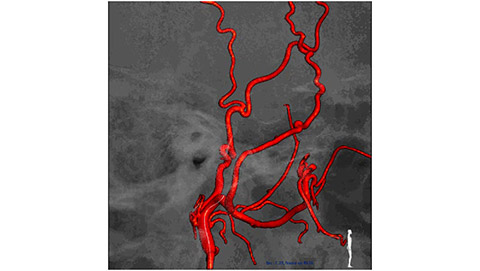

VasoCT (Allura X-ray system with dedicated EPX settings + XperCT + intravenous contrast injection) provides high-resolution imaging of intracranial arteries to help visualize location, size, and direction of an occlusion in case of Ischemic Stroke.

VasoCT visualizes small intra-cranial devices in vessel context with unmatched spatial resolution. Metal Artifact Reduction decreases streaking artifacts as from coil mass close to intra-cranial devices.